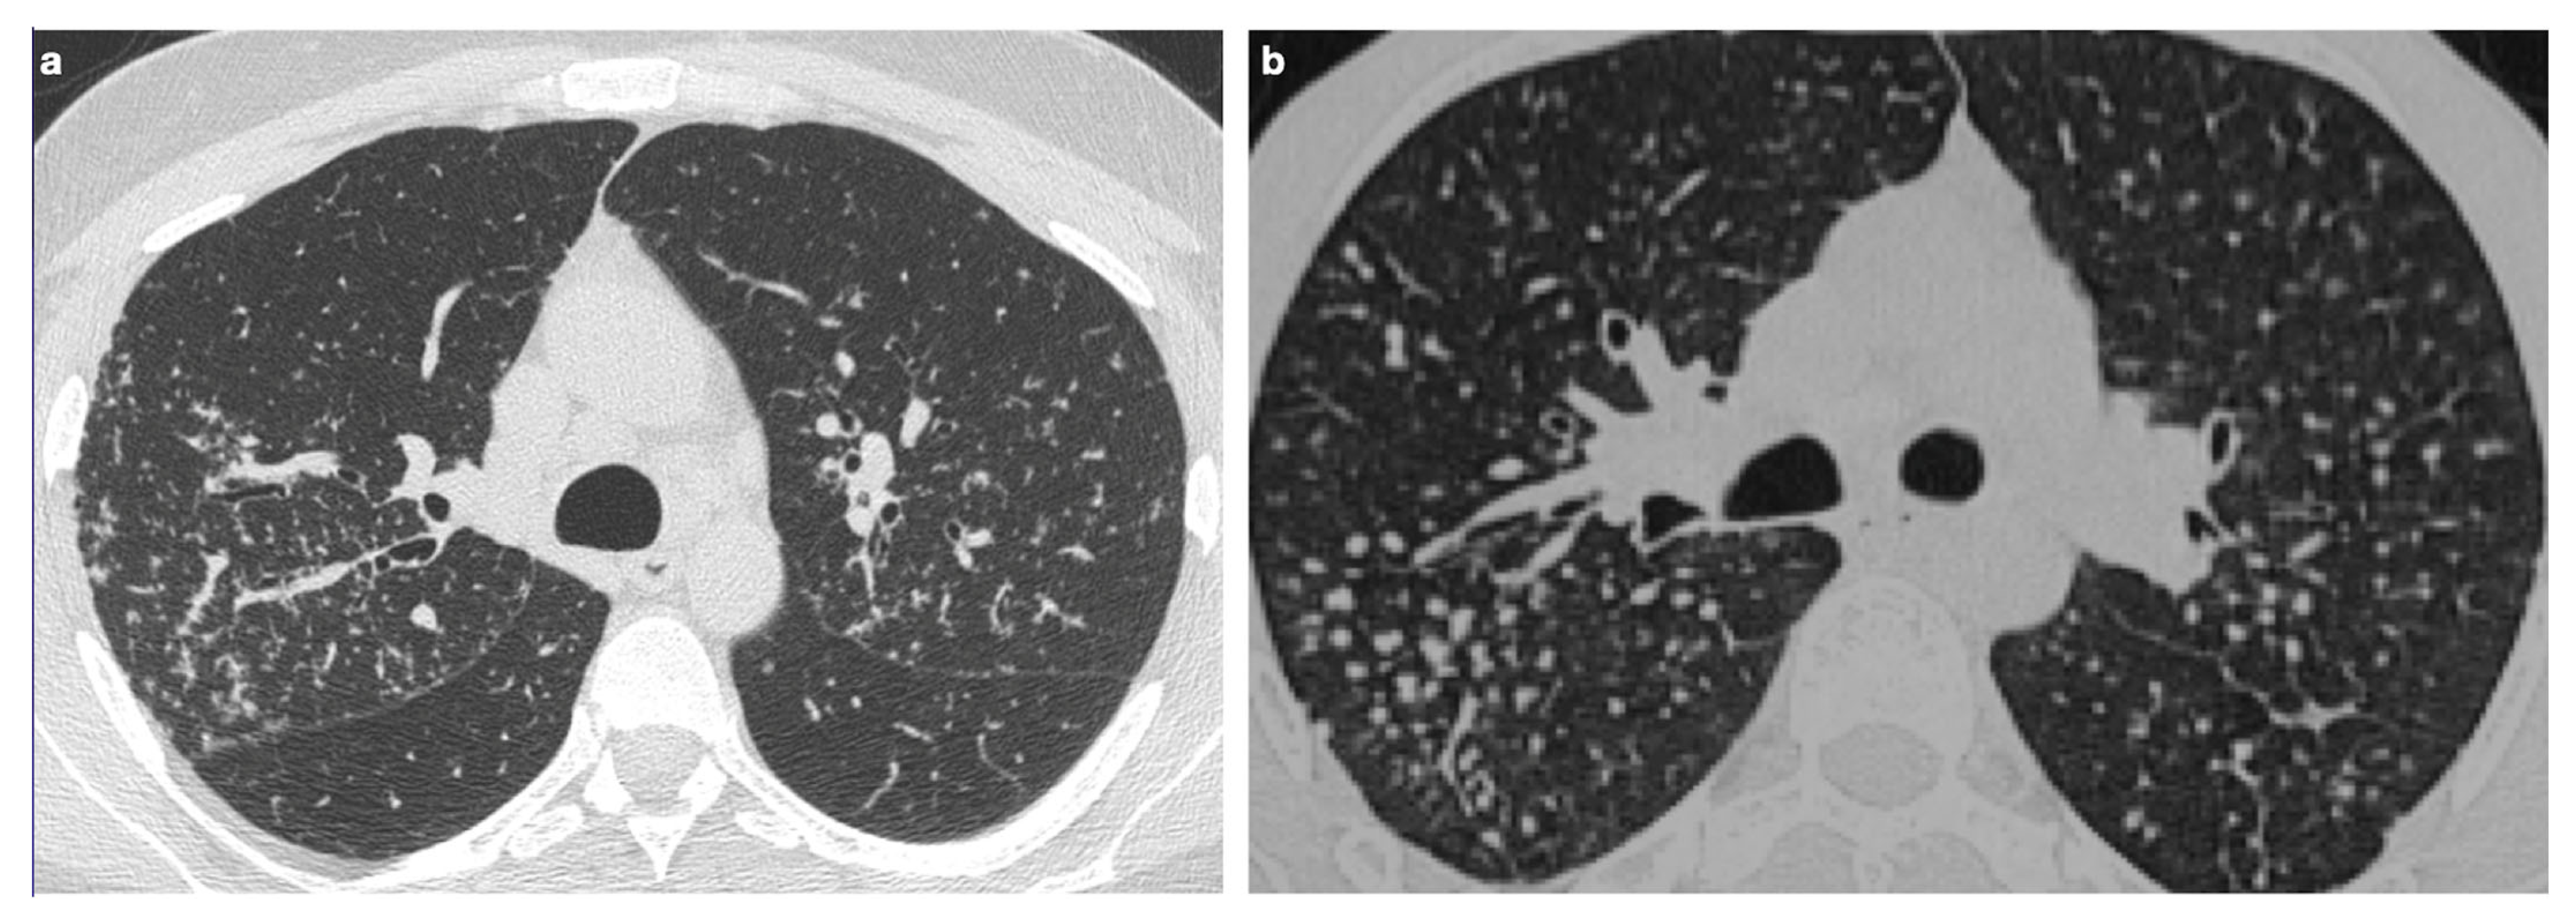

| Characteristic | Sarcoidosis | Pulmonary Metastases |

|---|---|---|

| Presence of nodules or masses | Rarely presents a single mass or solitary nodule | Frequently presents multiple well-defined, rounded nodules |

| Appearance of nodules | May have macronodules (>5 mm), multiple, well-defined, simulating metastases | Multiple, well-circumscribed nodules distributed across various lobes |

| Differential diagnosis | Difficult to distinguish from metastatic disease with imaging alone | Often requires exclusion of granulomatous diseases |

| Granuloma localization | Granulomas may appear near tumors, but also in distant sites | Metastatic nodules develop from a known or unknown primary tumor |

| Diagnostic strategy | Search for granulomas in other sites and confirm via biopsy/histology in doubtful cases | Diagnosis based on oncological history and histopathological confirmation, if necessary |